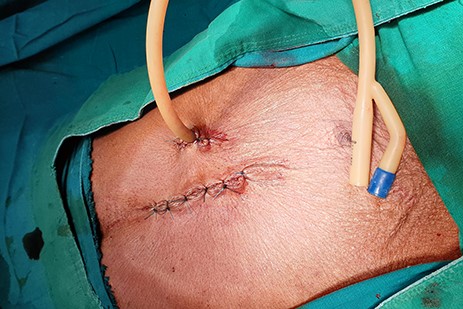

The patient was scheduled for GFT insertion, whereby a 24Fr urinary catheter was inserted via the paramedian incision into the stomach and secured using the Stamm technique (Fig. 2). Intraoperatively the liver had no lesions. The patient was sent to the general ward and semi-solid feeds were initiated through the gastrostomy feeding tube. The patient was discharged on the second day and was instructed to continue with semi-solid feeds, and wound dressing at a nearby health centre. The care-taker was clearly instructed to spigot the catheter after use and to flush the food contents with water after every meal to avoid blockage.

Patient was scheduled for GFT insertion, blood transfusion and hematemics were given and control haemoglobin obtained was 13.4 g/dl. Surgery was done and the findings were a collapsed stomach and a non-nodulated liver, a 24Fr urinary catheter was inserted, ballooned and secured using the Stamm technique (Fig. 5). Patient was transferred to the general ward and was discharged on the second day post-surgery.

The patient was scheduled for GFT insertion. Under aseptic technique, with the patient in supine position, 24 Fr urinary catheter as an improvised GFT was inserted in Stamm manner, haemostasis achieved, abdomen closed in layers and dressed (Fig. 9). There was no ascites and mesenteric lymph nodes were not palpable. After the procedure the patient was discharged home on the second day with analgesics and was booked for a surgical outpatient clinic appointment after 2 weeks.

24Fr urinary catheter as an improvised gastrostomy feeding tube.